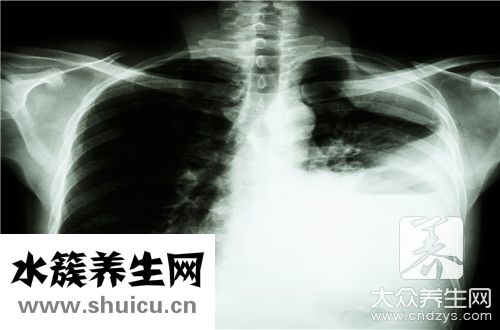

肺鈣化灶是肺實(shí)質(zhì)肺細(xì)胞發(fā)炎后產(chǎn)生的“疤”,一般無生命危險,一部分病人可能和肝內(nèi)膽管結(jié)石病人一樣會出現(xiàn)肺區(qū)悶脹覺得,如診斷一般不需醫(yī)治,肺內(nèi)有鈣化點(diǎn)可能是肺內(nèi)膽壁厚一部分增厚。肺內(nèi)血管影。

一切正常肺組織是由支氣管、支氣管炎支氣管、淋巴結(jié)、血管等構(gòu)成,呈淡粉色。若有非常總數(shù)和毒力強(qiáng)的結(jié)核菌入侵肺組織并在里面生長發(fā)育繁育,造成新陳代謝物質(zhì),使肺組織受到損壞,出現(xiàn)仿佛霉變的乳酪一樣的物質(zhì),使一切正常的肺組織構(gòu)造、生理作用消退。醫(yī)藥學(xué)上稱之為奶酪樣壞死。壞死物偏重于酸堿性,不容易汽化消化吸收,能長時間具有。在機(jī)體抵抗力強(qiáng),或是放療后,奶酪樣疾病中的結(jié)核菌新陳代謝消沉,繁育工作能力被消弱,疾病缺水而干躁,碳酸氫鈣和碳酸鈣粘附產(chǎn)生增厚。

實(shí)際上,大家每日吸氣的氣體里都可能帶有結(jié)核菌,因而感染結(jié)核菌也是很普遍的。只不過是大部分人到感染了結(jié)核菌之后,自身的人體抵抗能力十分強(qiáng),因此沒有生病,沒有主要表現(xiàn)出病癥,這稱為潛在性感染。僅有少數(shù)人感染結(jié)核菌后,會發(fā)展趨勢成肺結(jié)核。很多人去做透視,發(fā)覺肺臟有鈣化點(diǎn),這就表明其感染過結(jié)核菌。此外,一般的肺結(jié)核病人治愈后,肺臟也會留有鈣化點(diǎn),事實(shí)上,肺部鈣化點(diǎn)是肺結(jié)核治愈的方式之一。

肺臟別的感染性的發(fā)炎也是這般,例如得了肺炎的情況下,歷經(jīng)醫(yī)治,造成 發(fā)炎的病菌、病毒感染被殺掉了,但肺上也會留有鈣化點(diǎn)。

因此,一般來說,肺部鈣化點(diǎn)是良好的,只意味著以前的變病,對人體沒什么影響,不必太在意,更不必醫(yī)治。